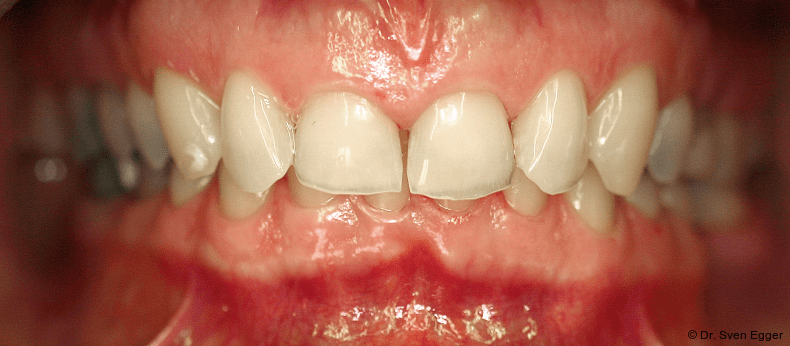

- Zahnlänge: Die Verlängerung der gesamten Oberkieferfront um ca. 1 mm empfindet die Patientin als sehr attraktiv, das entspannte Lächeln zeigt fast die gesamte Frontzahnreihe. Der Schneidekantenverlauf folgt der Konkavität der Unterlippe.

- Zahnform: Die größeren und längeren Schneide- und Eckzähne sowie die kleine Stellungskorrektur der beiden seitlichen Schneidezähne fügen sich harmonisch in das Gesamtbild der Restbezahnung ein und schenken der Patientin ein attraktives Erscheinungsbild (Abb. 15).

- Form und Größe, Charakterisierung durch den ausführenden Zahntechniker (Transparenz, Transluzenz) sowie die Oberflächenstruktur (Textur) der keramischen Veneers zeigen ein ansprechendes Erscheinungsbild. Das Längen-Breiten-Verhältnis beträgt nun circa 80 Prozent (Länge 11 mm, Breite 8 mm).

- Zahnstellung: Die leicht nach distal rotierten seitlichen Schneidezähne konnten durch die Einzelzahnrestaurationen etwas ausgeglichen werden. Durch die „Verlängerung“ der Eckzähne konnte gezielt eine gute Front-Eckzahn-Führung in die Veneerrestaurationen eingearbeitet werden.

- Zahnfarbe: Die Zahnfarbe entpricht ganz den Vorstellungen der Patientin (A2, VITA).

Zusammenfassung der ästhetischen Problematik: Es zeigt sich nun hinsichtlich der Länge (Lächeln), Form, Farbe, Stellung der Zähne sowie der rosa Ästhetik ein ansprechendes dentogingivales Erscheinungsbild. Die unteren Frontzähne haben leichten Kontakt auf den Palatinalflächen der oberen Eck- und Schneidezähne. Der Overbite beträgt 4 mm. Der Overjet 2 mm (Abb. 16+17).